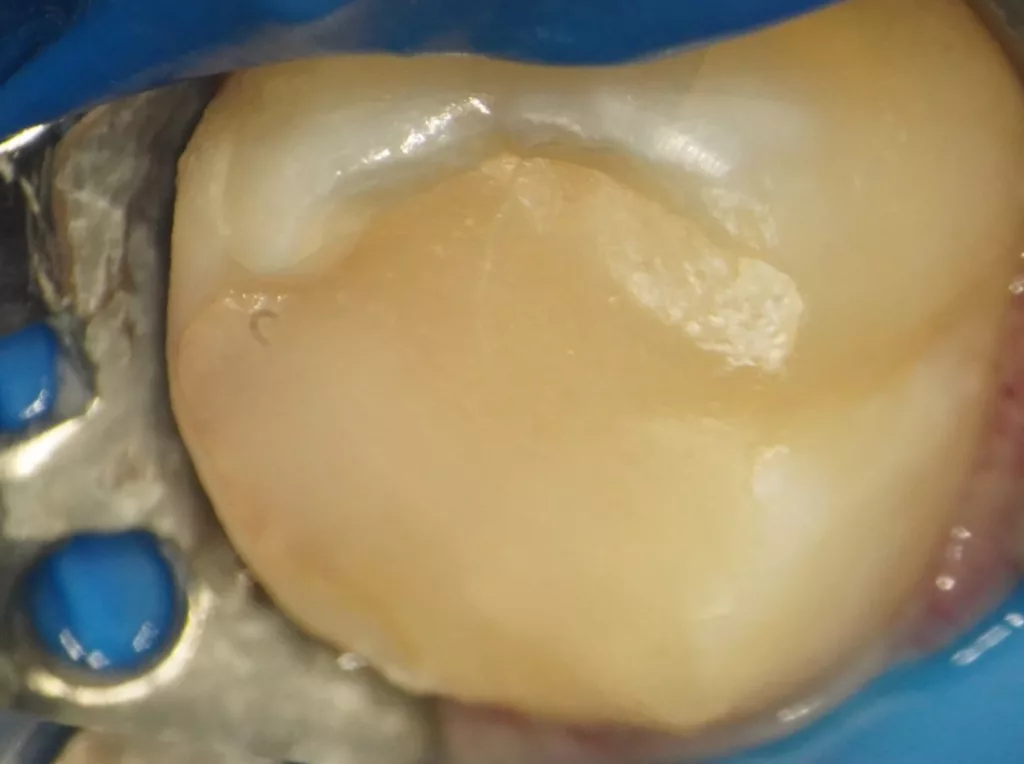

Im Rahmen der jährlichen Kontrolluntersuchung wurde bei einem achtjährigen Mädchen auf der routinemäßig angefertigten Röntgenaufnahme eine mittelgroße PEIR des Zahnes 46 (Grad 2 der Läsion nach Seow) entdeckt (Abb. 43). Die Patientin war komplett beschwerdefrei und der Zahnschmelz des betroffenen Zahnes sah intakt aus (Abb. 44 und 45). Weil auch hier der PEIR-Defekt gräulich durchschimmerte (Abb. 44 und 45) und der Zahn bereits seit einem Jahr durchgebrochen war, entschieden wir uns in diesem Fall, den Defekt klassisch mit Komposit zu restaurieren. Unter Lokalanästhesie mit Septanest 1/100 000 (Septodont, Frankreich) wurde zunächst Kofferdam mithilfe der Klammer U67 (KSK Dentech, Japan) gelegt (Abb. 45). Weder visuell noch mittels Sondierung konnte eine Verbindung zur Läsion festgestellt werden. Deswegen wurde an der Stelle, an welcher der PEIR-Defekt gräulich schimmerte, intakter Zahnschmelz der lingualen Querfissur entfernt (Abb. 46). Innerhalb der Läsion wurde nekrotisches intrakoronales Weichgewebe vorgefunden (Abb. 47), das problemlos mittels RONDOflex plus 360 (KaVo Dental, Deutschland) mit dem 27-µm-Pulver vollständig entfernt werden konnte. Der Boden des Defektes zeigte eine glatte, runde Form sowie helles, hartes und intaktes Dentin. Eine Präparation war nicht erforderlich, es wurde lediglich die Zahnschmelzkante geglättet (Abb. 48). Für die Restauration kamen erneut das Adhäsiv Optibond FL (Kerr, USA) und das Komposit Estelite ASTERIA OCE, A2B und Universal Flow AO2 (Tokuyama, Japan) zur Anwendung (Abb. 49). 6 Monate nach der Behandlung zeigte sich das Ergebnis sowohl aus klinischer als auch radiologischer Sicht stabil wie die Abbildungen 50 und 51 zeigen.

Das siebenjährige Mädchen wurde von einer Kollegin zur Behandlung einer atypischen intrakoronalen Aufhellung im Kronenbereich des nach Durchbruch befindlichen symptomatischen Zahnes 46 überwiesen (Abb. 20). Anamnestisch bestanden seit zwei Tagen kurzintervallige Spontan- und Nachtschmerzen, die mit Ibuprofen 40 mg/ml Kindersirup behandelt wurden. Das Röntgenbild zeigte einen umfangreichen runden Dentindefekt unter intaktem Zahnschmelz, der bis in das Pulpakavum reichte. Daraus ergab sich die Verdachtsdiagnose PEIR des Zahnes 46 (Grad 3 der Läsion nach Seow) in Kombination mit einer akuten Pulpitis. Nach Leitungsanästhesie am Foramen mandibulae mit Septanest 1/100 000 (Septodont, Frankreich) und STA-System (Milstone Scientific, USA) konnte der Zahn mithilfe von Kofferdam (Klammer U67, KSK Dentech, Japan) gut isoliert werden (Abb. 21). Um die ursprüngliche Zahnanatomie zu imitieren, wurde ein Okklusalstempel aus dem flüssigen Kofferdam OpalDam (Ultradent, Frankreich) und einem Microbrushapplikator angefertigt.